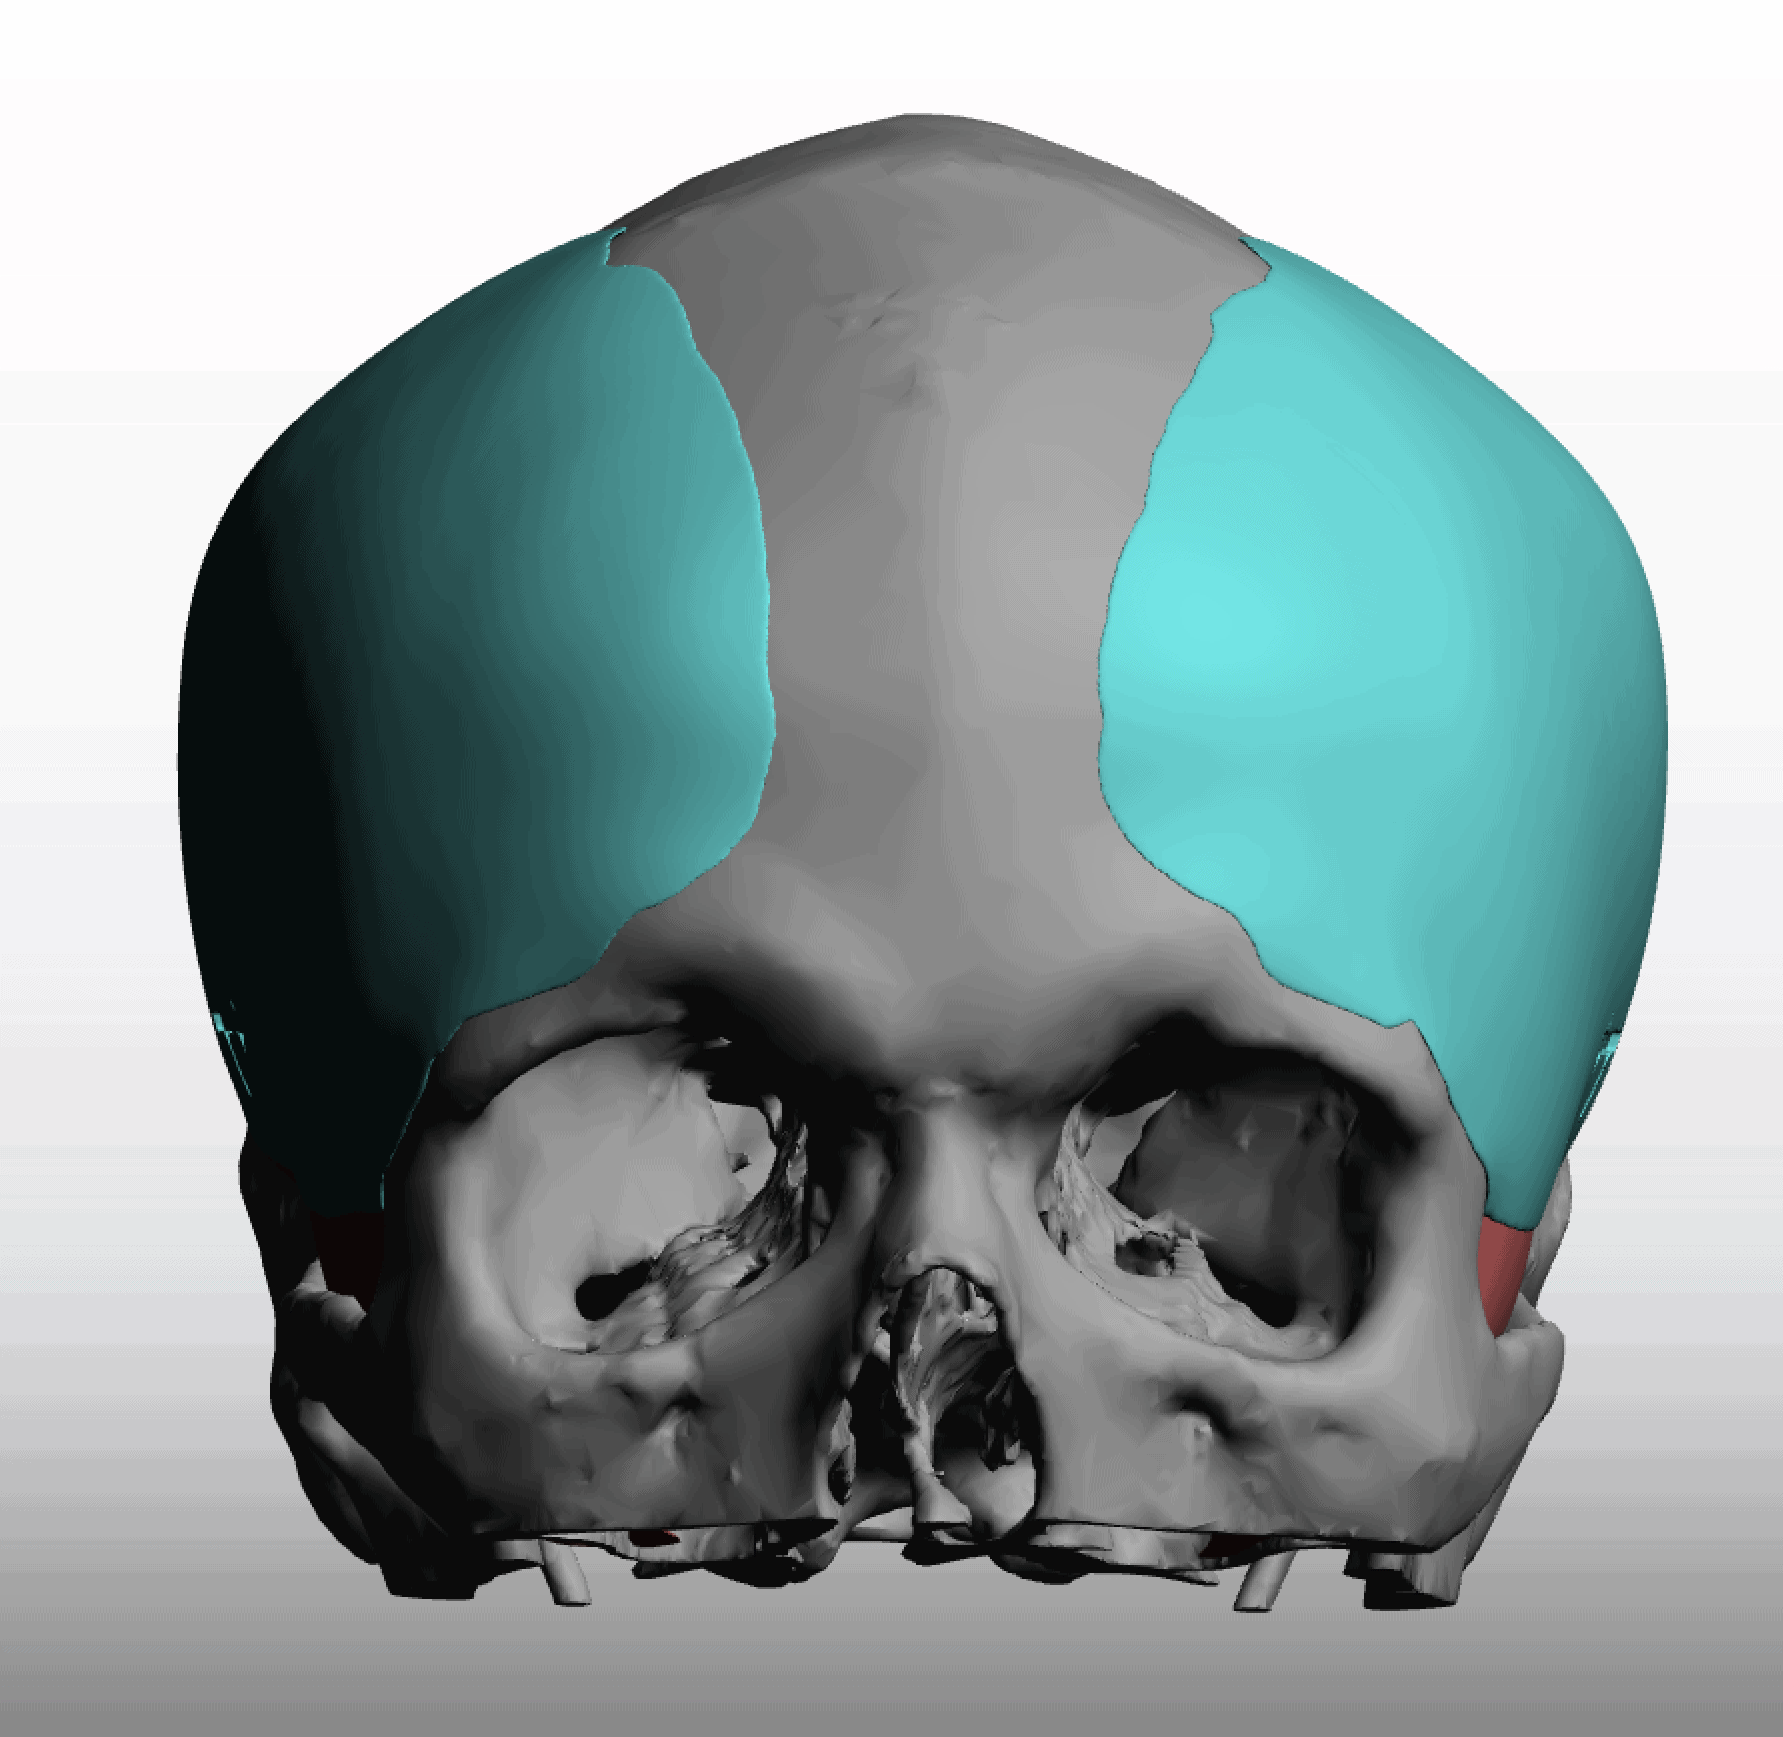

Desire for change of head shape from front view form an inverted V shape to a rounder and wider head shape.

Placement of custom extended forehead-temporal implants through incisions in the crease behind the ear. (he had a prior back of head skull implant which is green in the implant designs and which the head widening implants partially covered it)

Desire for change of head shape from front view form an inverted V shape to a rounder and wider head shape.

Placement of custom extended forehead-temporal implants through incisions in the crease behind the ear. (he had a prior back of head skull implant which is green in the implant designs and which the head widening implants partially covered it)